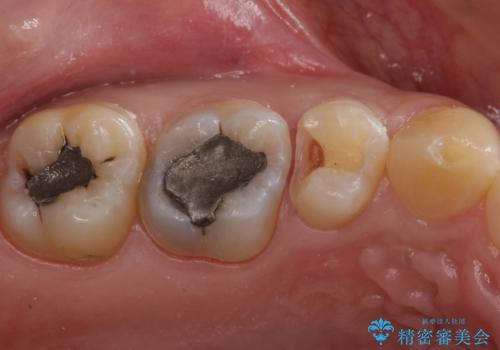

まだ虫歯が大きくなる前に処置をすることができたため神経の治療をせずに済みました。

歯と歯の間・適合の悪い修復物とその歯の間は虫歯ができることが多い場所になります。

修復物と歯の間の虫歯は、丁寧な虫歯除去と精密な修復物を装着することで予防することができます。